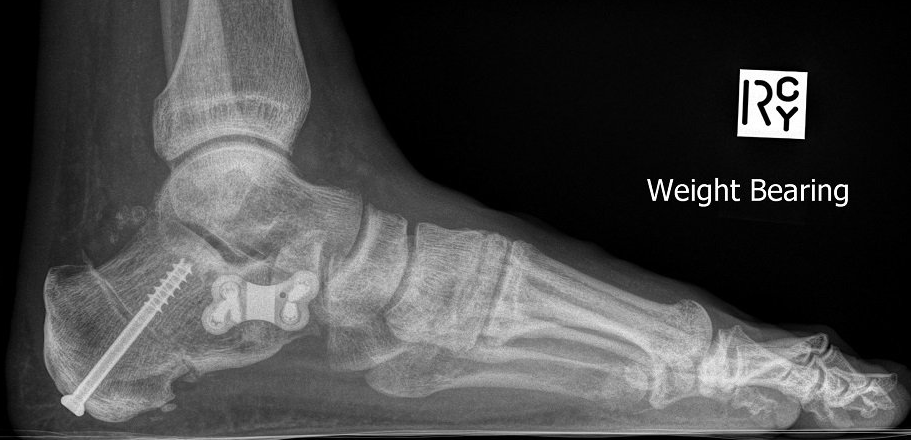

Flat foot surgery in adults is a multi-level procedure

aiming to simultaneously correct calf tightness, bone alignment, joint stability and tendon function.

- spring ligament repair vs sinus tarsi implant

- calcaneal osteotomy vs hindfoot fusion

- Cotton osteotomy vs midfoot fusion.